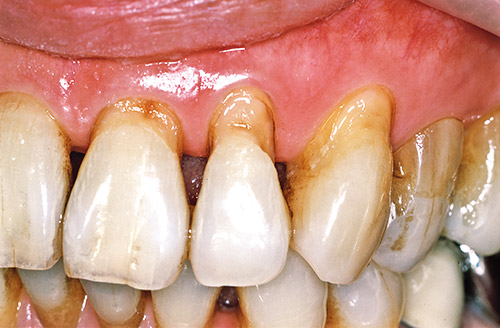

図1 左側前歯部3歯の露出根面のう蝕の術前。

図12 右側前歯のメタルボンド修復歯の歯頸部根面露出とう蝕の症例。